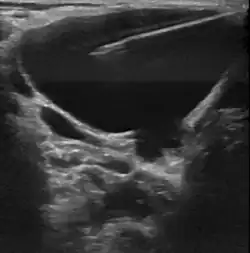

Пороки развития лимфатических сосудов в области головы и шеи чаще всего определяются при рождении или в первые годы жизни ребёнка, в возрасте до одного года в 60-80 % случаев[6]. Основными методами визуализации лимфатической мальформации являются ультразвуковое исследование (УЗИ) и магнитно-резонансная томография (МРТ). Данные исследования позволяют определить площадь и объём патологических тканей, размеры кист, топографию образования.

• Склеротерапия (склерозирование). Процедура включает в себя аспирацию содержимого кисты с последующей инъекцией склерозирующего агента, который вызывает рубцевание прилежащих стенок кисты. Склеротерапию проводят под ультразвуковой навигацией или с использование ЭОП’а. Склеротерапия не удаляет лимфатическую мальформацию, но она эффективно уменьшает объём поражения. Склеротерапия является методом выбора для лечения больших или проблемных крупно кистозных или смешанных лимфатических мальформациях[21].